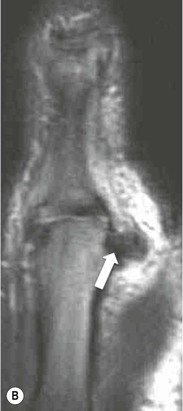

In acute injuries MRI shows the presence of soft-tissue oedema and haemorrhage around the affected ligament. MR arthrography may be preferred for diagnosis of chronic tears. Acute ulnar collateral ligament (UCL) tears often occur at the proximal origin on the medial humeral epicondyle (Fig. 46-23). In chronic tears the defect is usually at the insertion on the sublime tubercle of the ulna.14